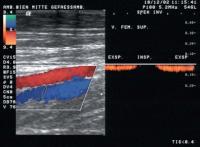

Duplexsonographie - V. fem. sup.

Abbildung 8: Dopplerkurve einer gesunden V. fem. sup. bei Provokation; Flußstop bei Valsalvamanöver

Keywords: DuplexsonographieValsalva-ManöverVena femoralis superficialis